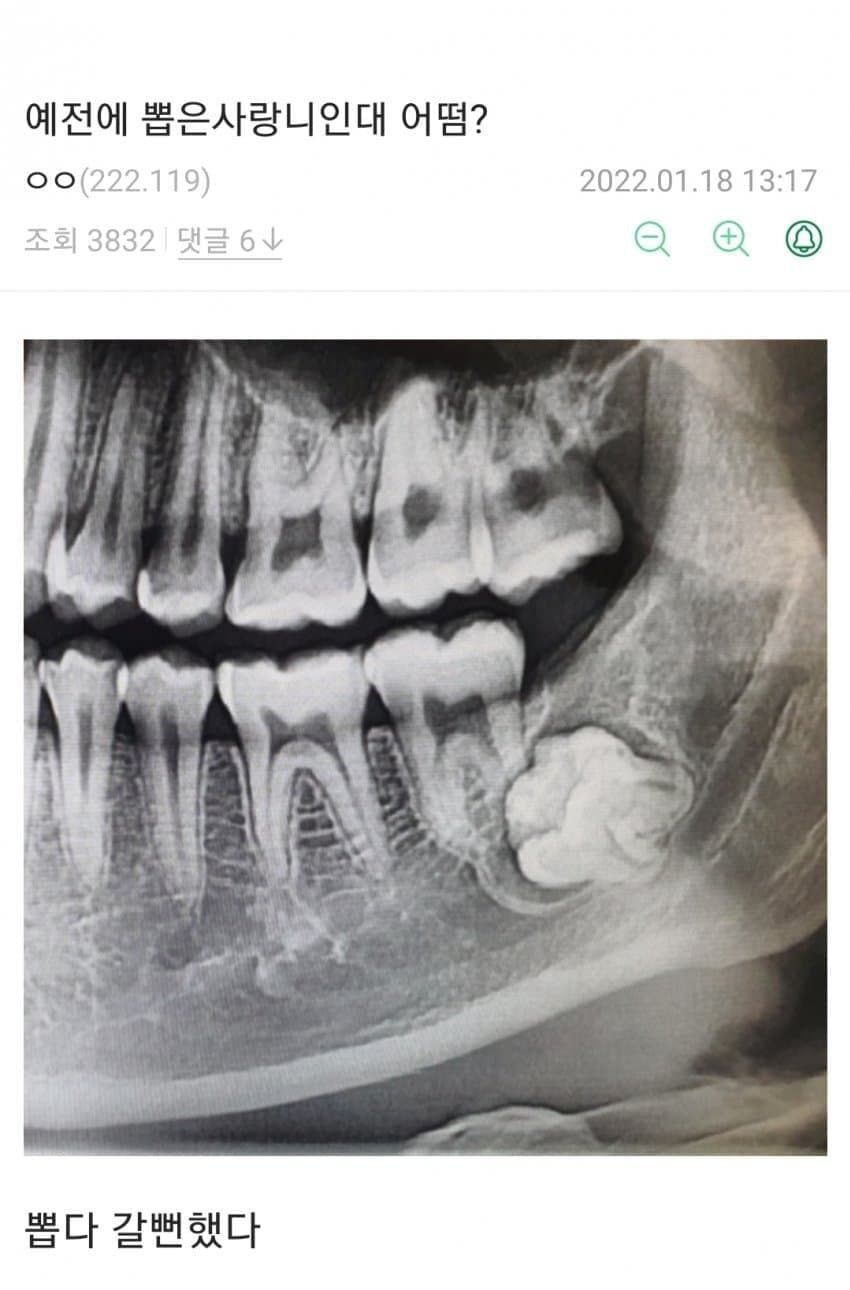

환자도 울고 의사도 울고

다들 전생에 무슨 죄를 지었길래 ㄷㄷㄷㄷㄷ

https://cafe.daum.net/dotax/Elgq/4528425?svc=daumapp 그리고 뽑고 희열 오졌을것 같은 치과의사

보기만해도 두통이ㄷㄷㄷ